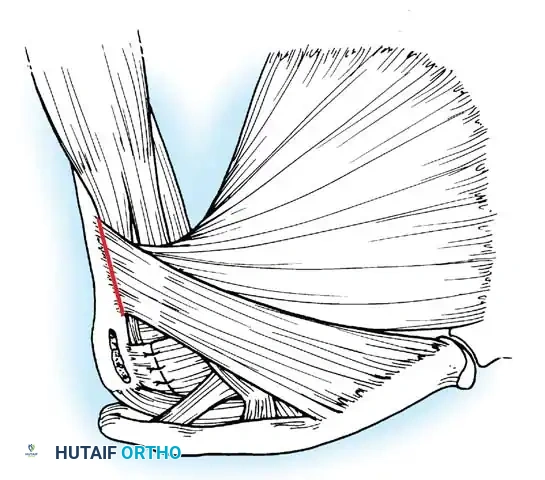

Subscapularis Management

Exposure of the anterior capsule requires navigating the subscapularis muscle. Historically, a vertical tenotomy was performed; however, modern techniques favor a subscapularis split or a peel to preserve the integrity of the muscle belly and its tendinous insertion.

- The Split: A horizontal split is made in the subscapularis at the junction of its middle and inferior thirds, extending from the lesser tuberosity medially.

- Separation: The subscapularis is carefully elevated off the underlying anterior joint capsule. This plane can be scarred in revision cases, requiring meticulous sharp dissection to avoid inadvertent capsulotomy.